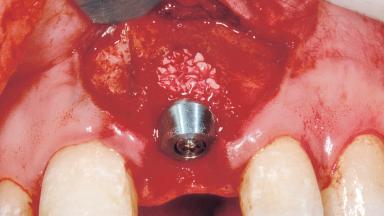

A 33-year-old female patient presented with an upper left central incisor that required extraction after a failed endodontic therapy. The tooth had been traumatized when the patient was a teenager and had undergone several endodontic treatments, including two apicectomy procedures. The patient was in good health and did not smoke. Clinical examination showed that the patient had a high lip line. In full smile, the gingival margins of the upper teeth were visible to the first molars. The gingival margins of central incisors 11 and 21 were only just showing. Examination of tooth 21 confirmed that the tooth was mobile and had hypererupted by 1 mm.